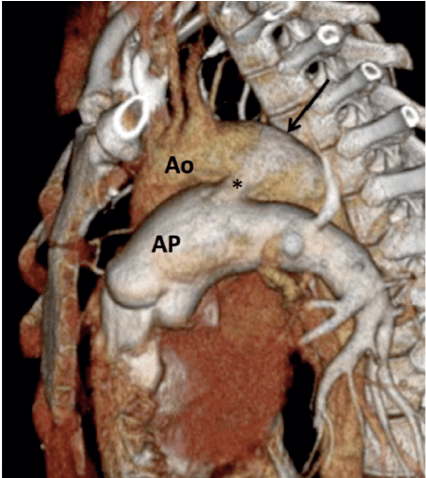

Estrutura vascular que conecta a aorta descendente à artéria pulmonar principal próximo à destino da artéria pulmonar esquerda.